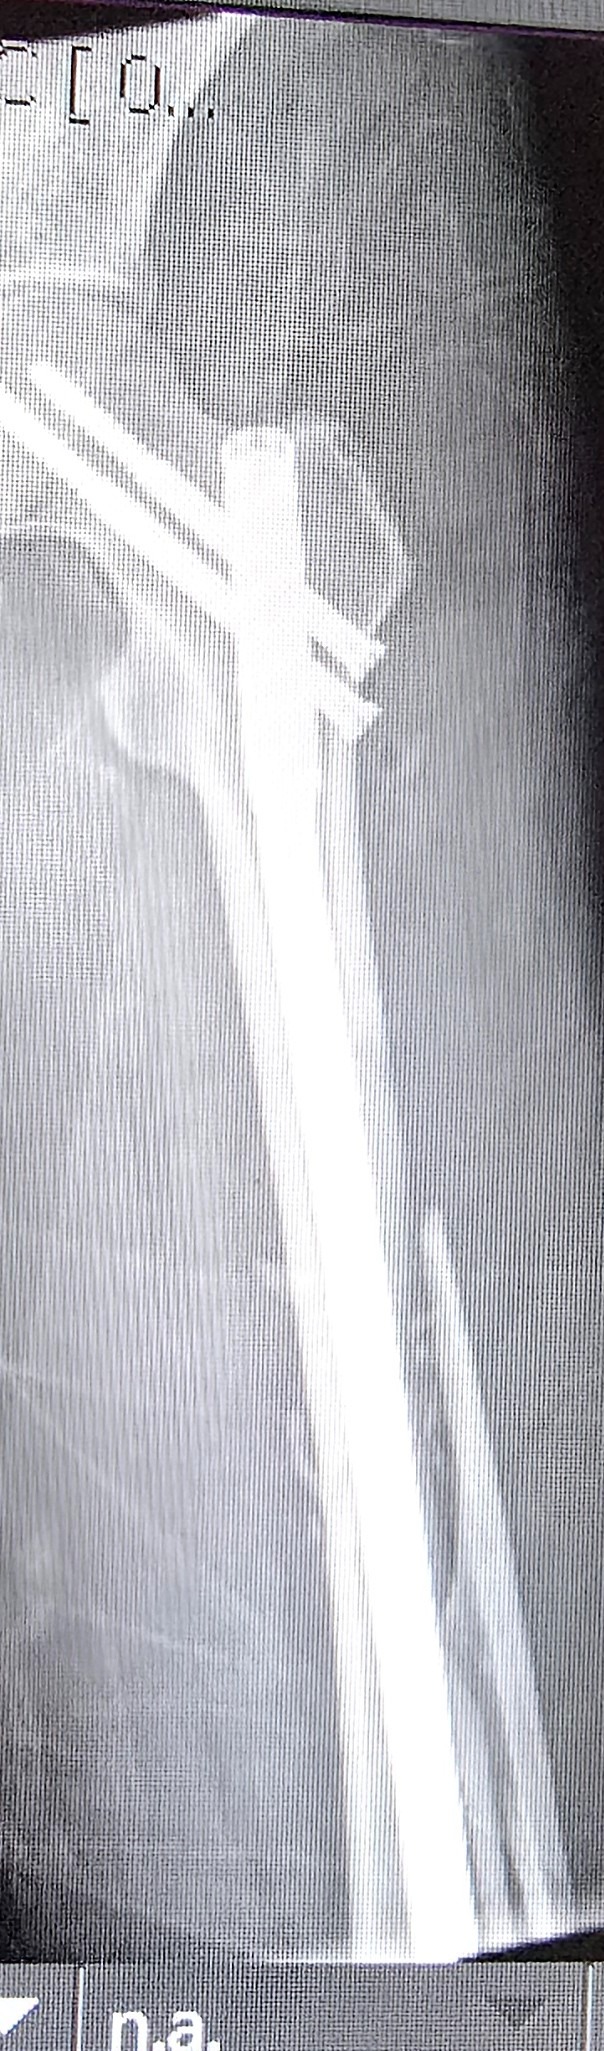

Even though he was wearing his seatbelt, the entire impact hit his left side. His left arm was shattered into multiple pieces, causing severe nerve damage. His left femur was broken into three pieces. He also struck his head against the window.

He was rushed to the hospital, where he spent a long night in unbearable pain before undergoing nearly eight hours of emergency surgery the next morning. Surgeons worked tirelessly to reconstruct his arm and leg. Today, Cole lives with metal rods and screws permanently placed in both his arm and leg.